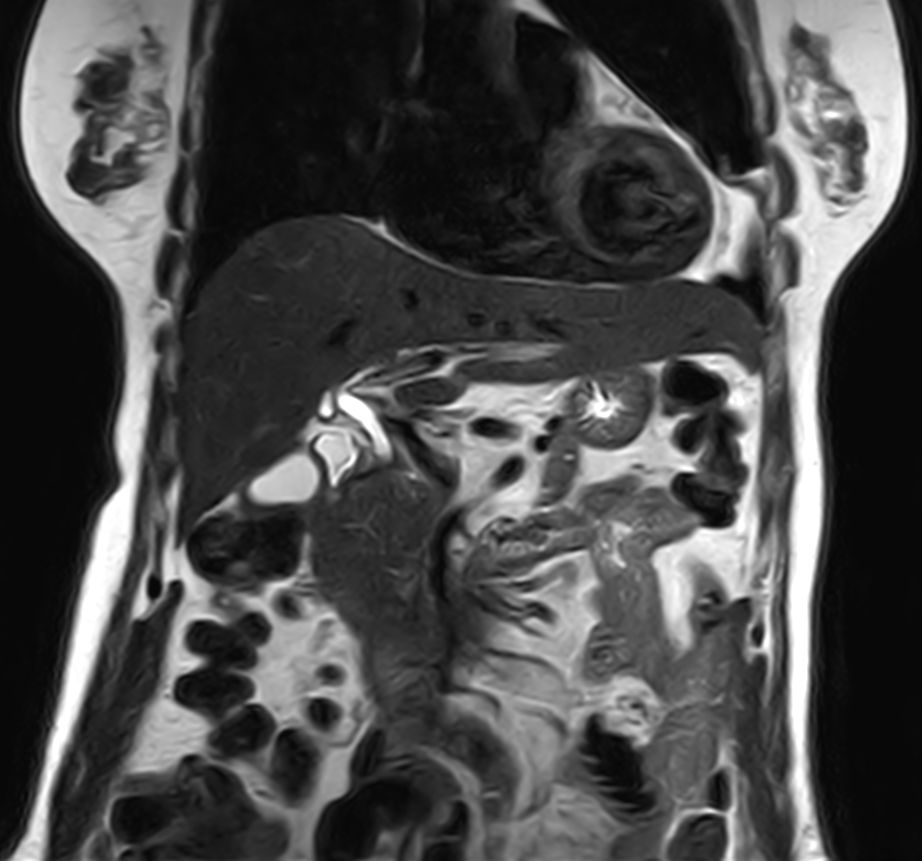

Pancreas nodule – Free breathing

Patient with a pancreas nodule. ExamCard includes Compressed SENSE to shorten the breath hold time, VitalEye for touchless respiratory sensing, MultiVane XD to acquire motion-free diagnostic images and 4D FreeBreathing to perform multi-phase contrast-enhanced Liver MRI studies.

T2w TSE MultiVane XD - Free Breathing (VitalEye)